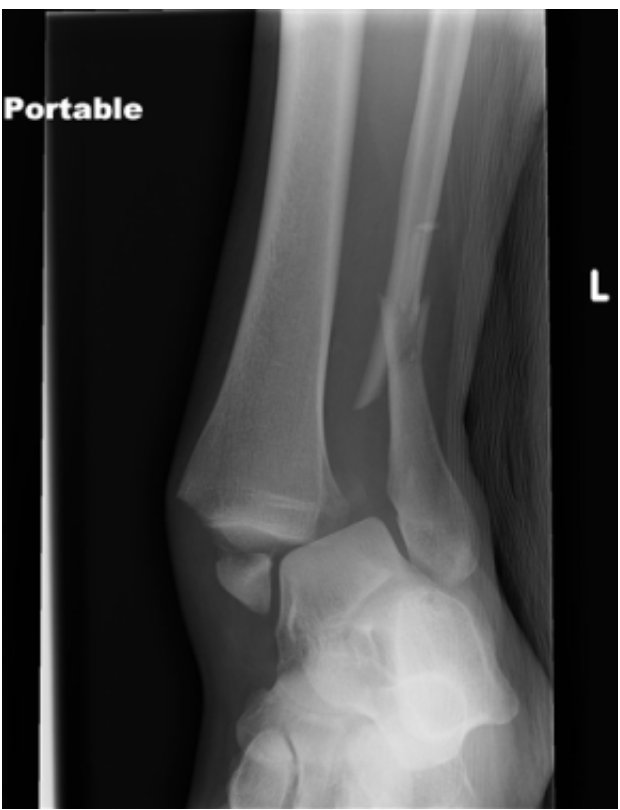

The tourniquet was brought down to evaluate the bleeding source. There was no active bleeding, neurological exam remained the same. Bedside XR was performed, showing displacement and fractures of the tibia and fibula.